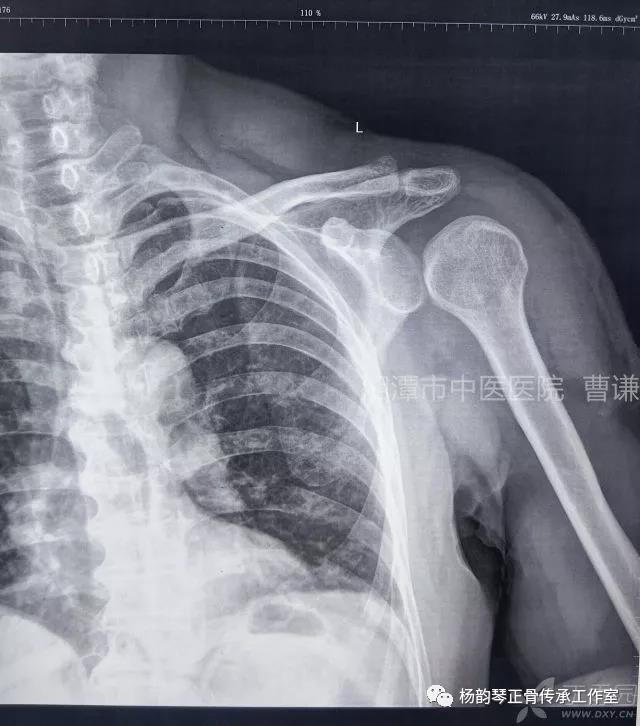

简要病史:骑摩托车跌倒致左肩部肿痛,活动受限,就诊于当地医院,拍片及磁共振检查后诊断为肩袖损伤及肩关节半脱位,予以悬吊固定,因症状缓解不明显就诊于我院。外院拍片情况如下:

应该说是一个典型的“灯泡征”影像,但是并未引起注意。

当地接诊医生应该说还是很负责的,同时拍了健侧片对比:

影像科报告,骨科医生光看报告行吗?